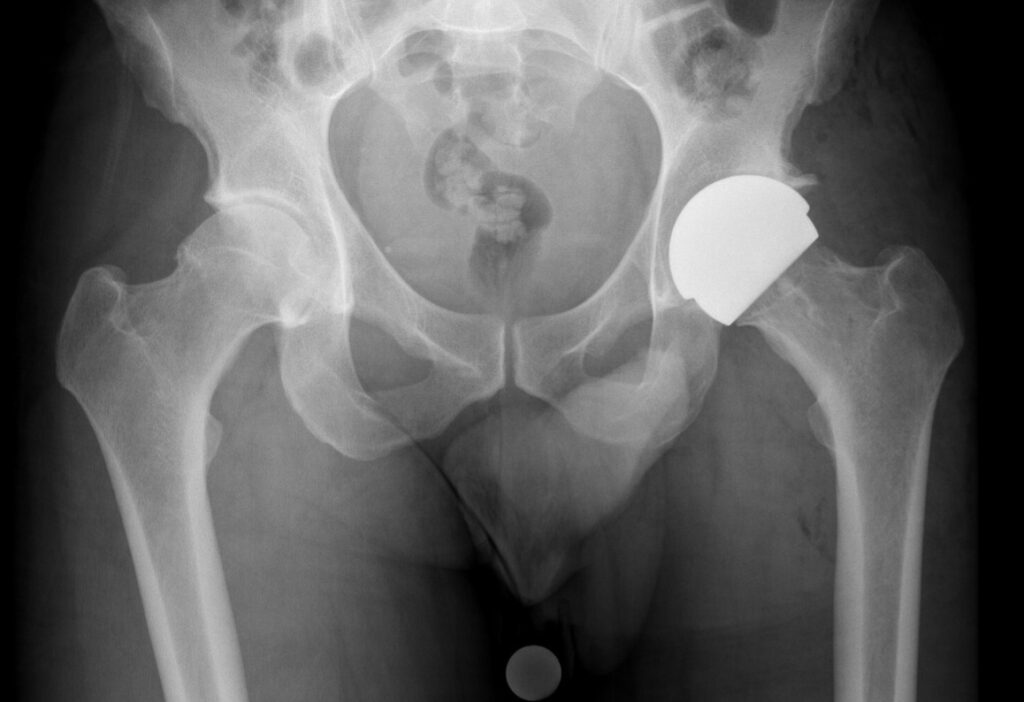

X-ray showing a ceramic-on-ceramic hip resurfacing implant in place, preserving the femoral head and neck

Hip resurfacing is an alternative to total hip replacement for younger, active patients with good bone quality. Rather than removing the entire ball of the femur, the femoral head is shaped and capped with a smooth metal surface, and the socket is replaced with a metal cup. This preserves more of your natural bone and allows for a larger, more stable bearing.

Historically, hip resurfacings have been made from metal components, which was associated with a higher rate of failure in women and smaller men. However, with the release of ceramic resurfacing components, current evidence suggests that the modes of failure associated with metal components has been negated.